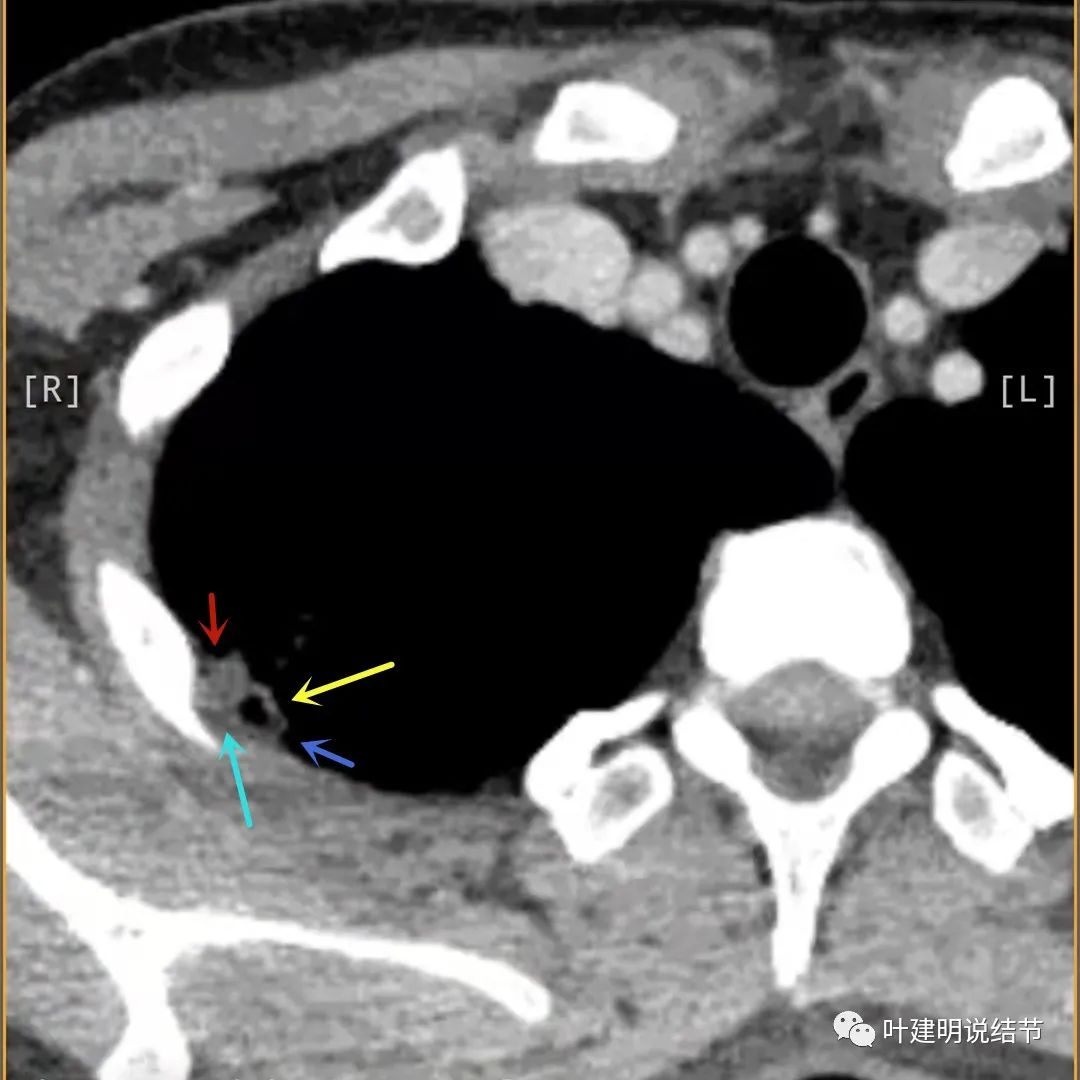

病灶有空洞(黄色箭头),主病灶边上见条索状高密度影(细红色箭头),邻近胸膜有粘连(蓝色箭头)

病灶有明显强化(说明炎性可能性大,如果恶性这样强化,血供丰富,应该倍增速度更快。蓝色箭头示胸膜处低于软组织密度的区域;桔色箭头示病灶边缘平直缺乏膨胀性;黄色箭头示中间的空腔